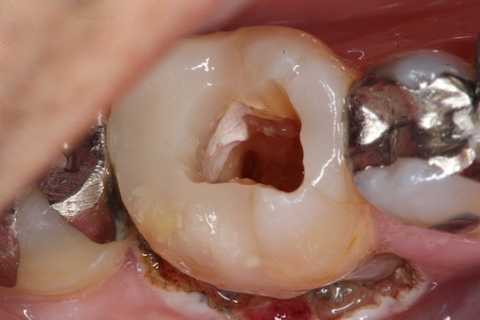

残根上のCR8 2025.10.28